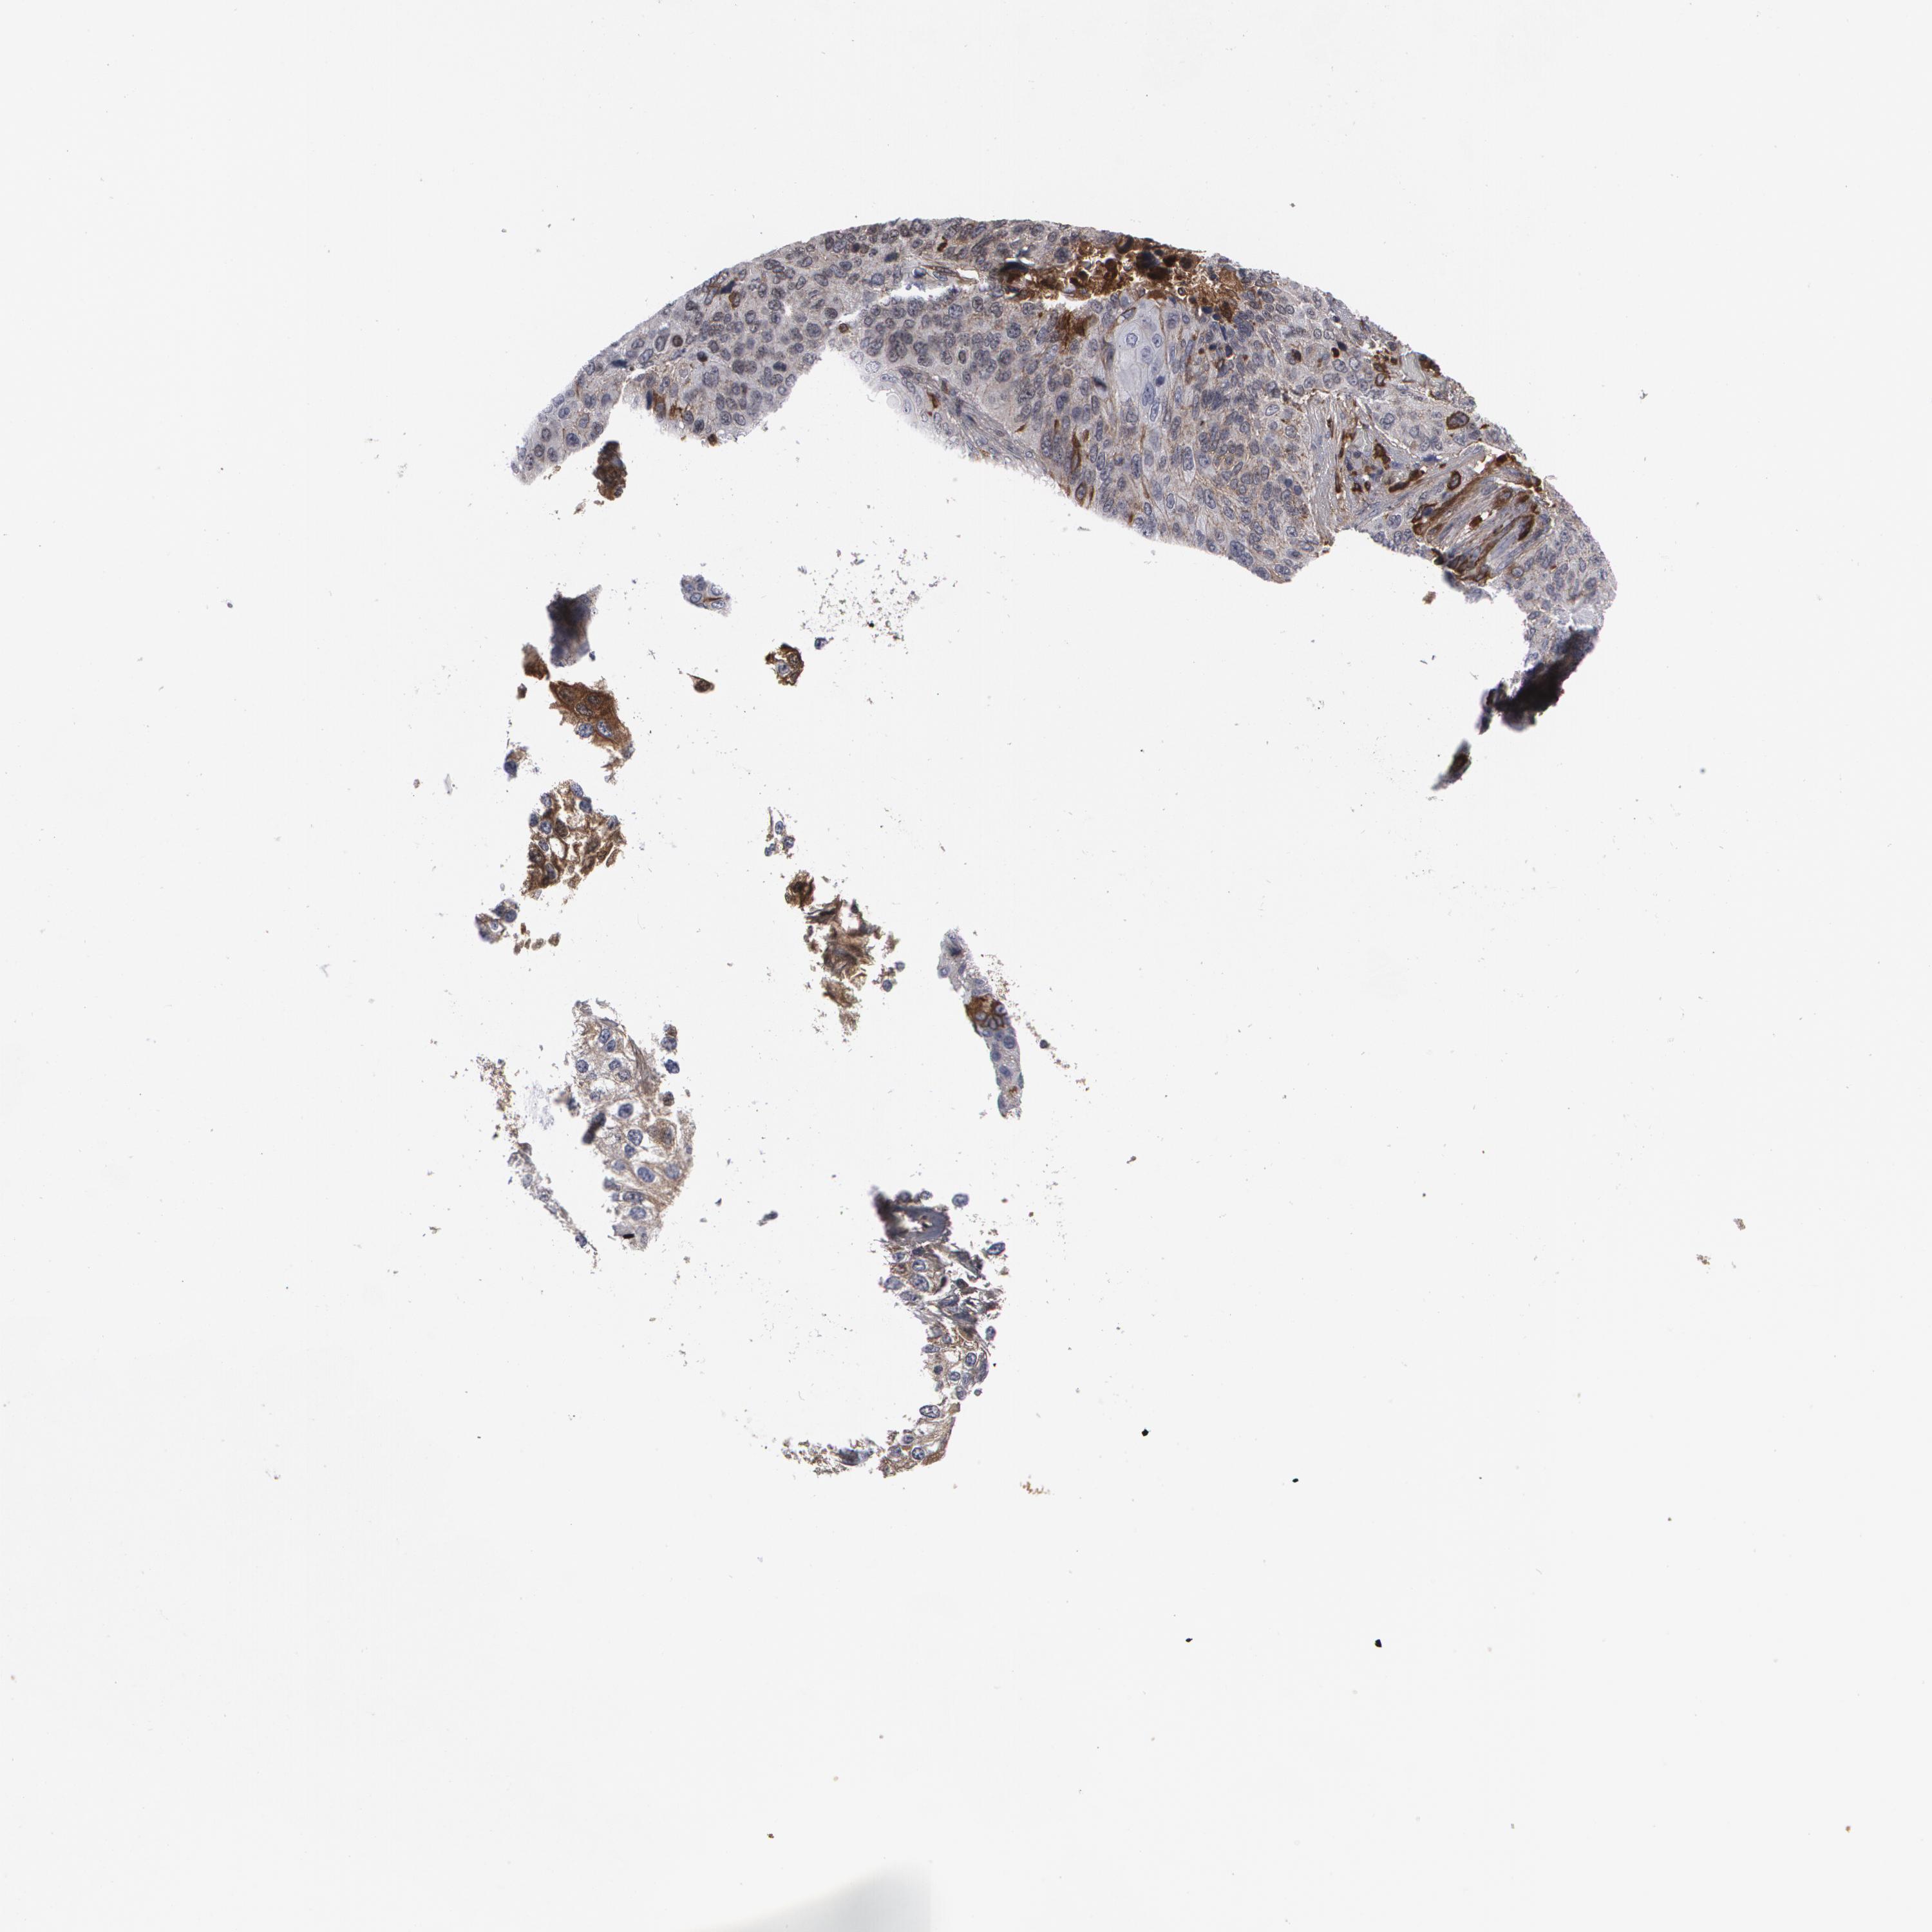

LUNG ADENOCARCINOMA (VALIDATION) - Interactive survival scatter ploti

The Survival Scatter plot shows the clinical status (i.e. dead or alive) for all individuals in the patient cohort, based on the same data that underlies the corresponding Kaplan-Meier plots. Patients that are alive at last time for follow-up are shown in blue and patients who have died during the study are shown in red.

The x-axis shows the expression levels (FPKM) of the investigated gene in the tumor tissue at the time of diagnosis. The y-axis shows the follow-up time after diagnosis (years). Both axes are complimented with kernel density curves demonstrating the data density over the axes. The top density plot shows the expression levels (FPKM) distribution among dead (red) and alive patients (blue). The right density plot shows the data density of the survived years of dead patients with high and low expression levels respectively, stratified using the cutoff indicated by the vertical dashed line through the Survival Scatter plot. This cutoff is automatically defined based on the FPKM cutoff that minimizes the p-score. The cutoff can be changed by dragging the vertical line or by entering a cutoff value in the square labeled "Current cut-off".

Under the Survival Scatter plot the p-score landscape (black curve; left axis) is shown together with dead median separation (red curve; right axis). Dead median separation is the difference in median mRNA expression between patients who have died with high and low expression, respectively. It is calculated as follows: median FPKM expression of dead patients with high expression - median FPKM expression of dead patients with low expression. This is intended to aid the user in visually exploring custom cutoffs and the associated p-scores and dead median separation.

Individual patient data is displayed and can be filtered by clicking on one or more of the category buttons on the top of the page. Categories describing expression level and patient information include: high, low, alive, dead, female, male and tumor stages. The scale of the x-axis can be toggled between linear and log-scale by clicking on the "x log" button. Mouse-over function shows TCGA ID, patient information and mRNA expression (FPKM) for each patient.

& Survival analysisi

Kaplan-Meier plots summarize results from analysis of correlation between mRNA expression level and patient survival. Patients were divided based on level of expression into one of the two groups "low" (under cut off) or "high" (over cut off). X-axis shows time for survival (years) and y-axis shows the probability of survival, where 1.0 corresponds to 100 percent.

LRG1 is not prognostic in Lung Adenocarcinoma (validation)

: 16.06

Average pTPM 15.8

Number of samples 105